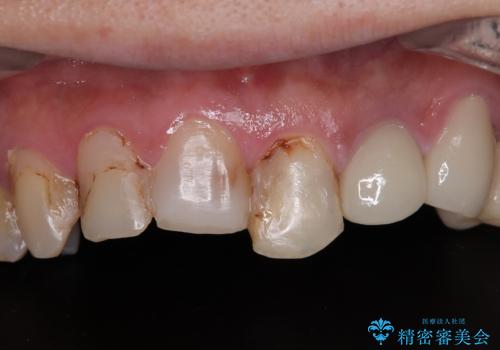

- すぐに欠けてしまう前歯や、むし歯で全顎的に処置された歯を気にして来院された患者様です。

元来むし歯が多く、さらに受け口傾向の咬み合わせを気にしていらっしゃいました。

当初はむし歯処置が必要な歯のみの治療予定でしたが、捻転や咬み合わせを可及的に改善したいとのことで、全顎的にオールセラミッククラウンにて補綴治療を行うこととしました。